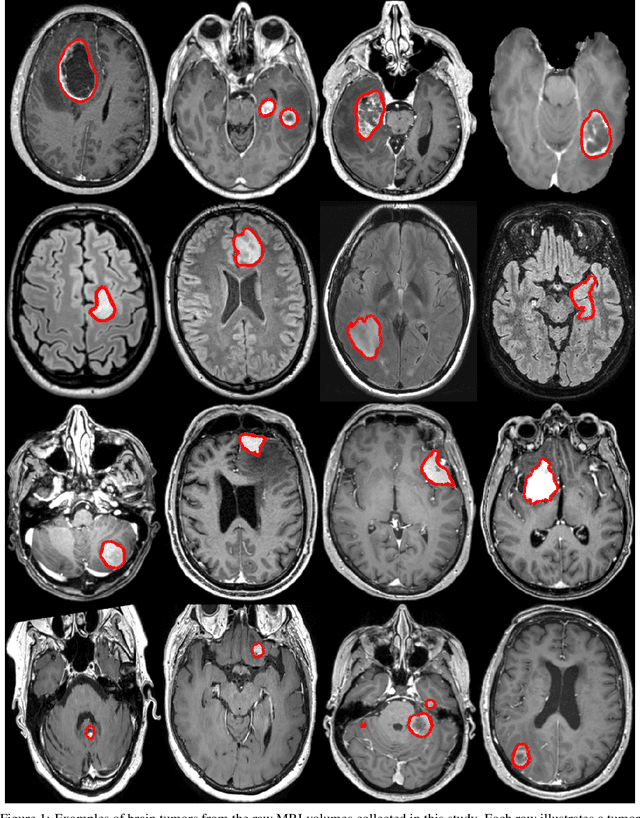

Figure 1 for Preoperative brain tumor imaging: models and software for segmentation and standardized reporting